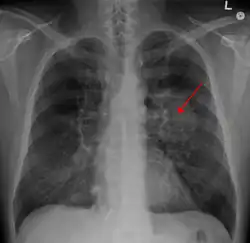

Having been previously physically fit and never smoked, in 2017 Cosford was diagnosed with lung cancer.[27][50] Cosford was an active cyclist, having spent years cycling in London traffic on his Brompton folding bicycle.[1][51] He had previously cycled from London to Berlin, and completed the Paris-Brest-Paris ride within 90 hour, and cycled between Land’s End and John O’Groats within a week.[4][52] Six months prior to his diagnosis he had been training on 600 km bike routes.[1][51] Following some shortness of breath on exertion, a chest X-ray confirmed a large collection of fluid in the lung with a collapsed left lung.[51] The diagnosis was an inoperable lung cancer accompanied by spread to the liver.[51] Although he could not prove it, he suspected that air pollution in London contributed to his diagnosis and stated that "of all the risk factors, air pollution seems to me the most likely cause of my own disease."[53][54] In 2018, he delivered his first public speech on his diagnosis at the Royal Society of Medicine, in London.[51]